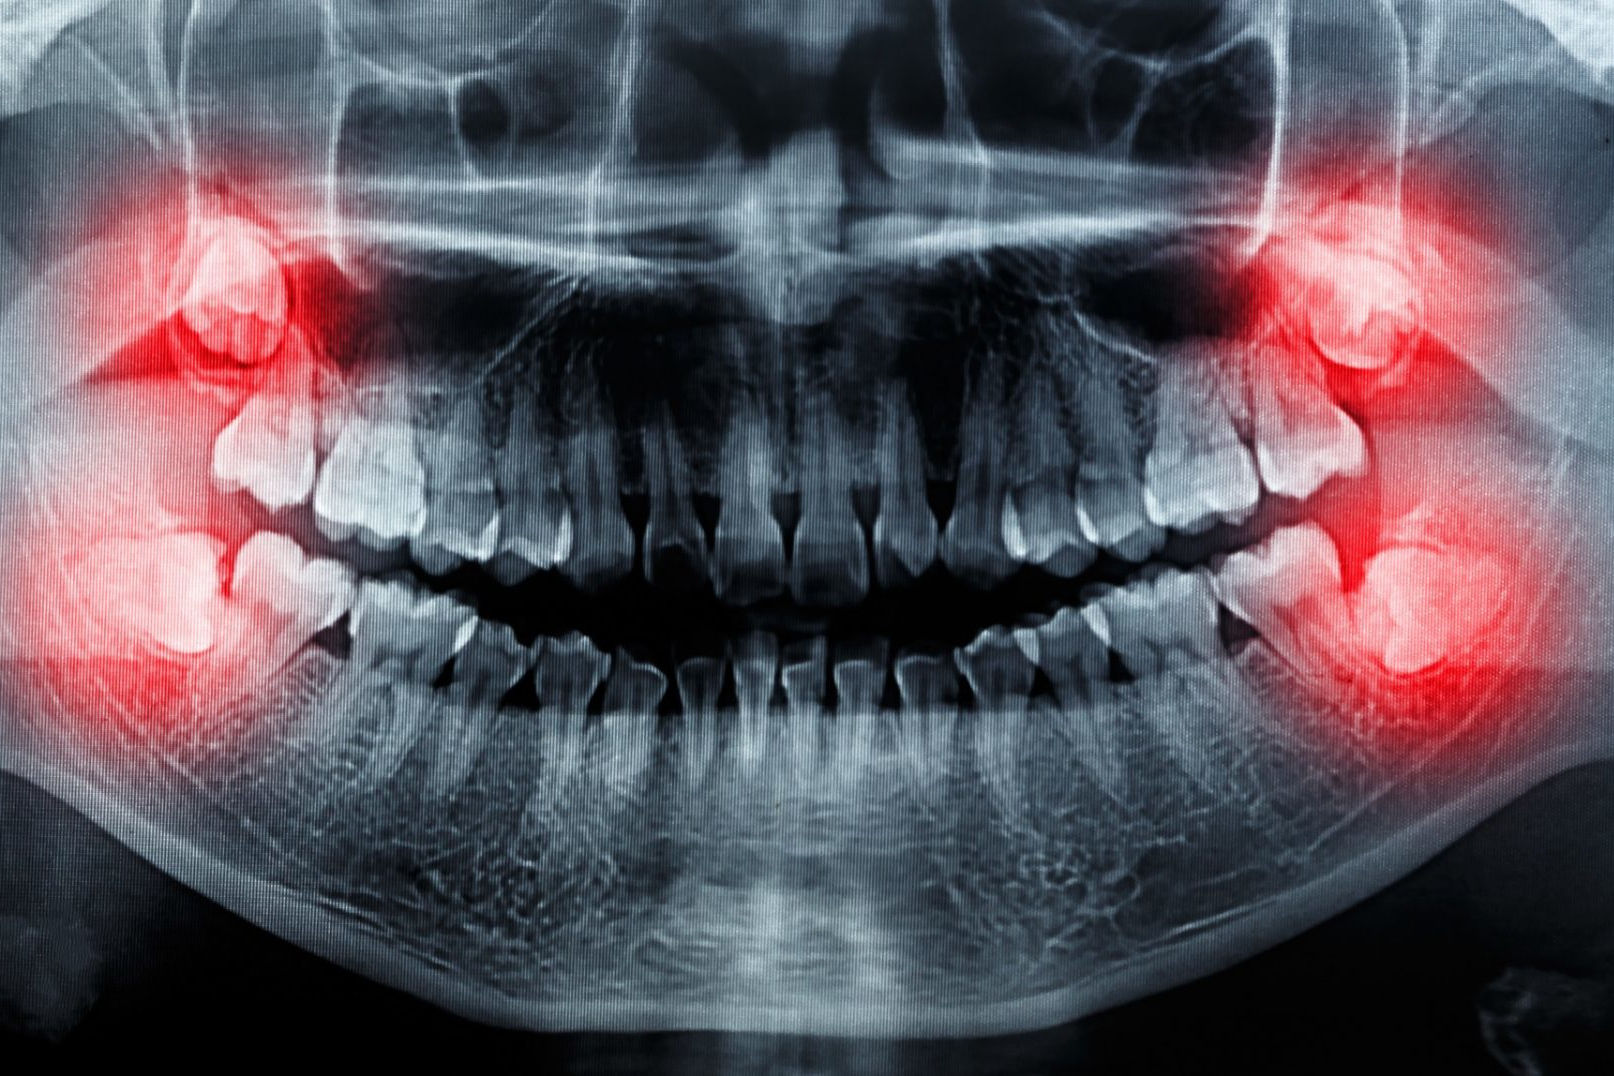

Surgical extractions – removal of wisdom teeth

Wisdom teeth are usually firmly anchored, have 3-4 roots, and require surgical treatment to be removed. Furthermore, we often find that wisdom teeth grow inwards, are deeply imbeded in the jawbone and their position usually deviates from the normal. The reason behind it is that the facial skeleton, especially the jaw, has become smaller over the millennia, leaving less space for the same number of teeth. It is becoming increasingly common for wisdom teeth not to form at all.

What symptoms can occur with wisdom teeth and why?

If a wisdom tooth cannot grow out completely and remains partly under the gum, it can become inflamed. Cleaning these teeth can also be complicated, which can cause additional inflammation, even under the palate. This can cause pain, tooth decay, and bad breath.

Wisdom teeth in poor positions can also have a negative effect on the denture as it puts a pressure on the teeth next to it. This can lead to misalignment or crowding on full set of teeth. In these cases, braces are recommended for correction.